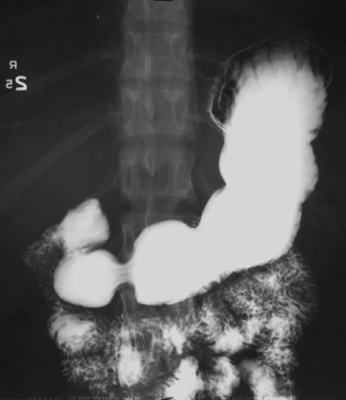

Following the DC examination of the esophagus and stomach, perform

single-contrast graded-compression (SCGC) spots. Turn patient into

right anterior oblique (RAO) position. Place compression paddle beneath

patient and inflate balloon for graded compression of duodenal bulb. Take

one SCGC spot (Zoom to 6" or 9" FOV) of duodenal bulb and one SC spot of

distended proximal duodenal loop.

- Turn x-ray table upright. Use compression cone on fluoroscope to

obtain graded compression of duodenal bulb. Take two SCGC spots (Zoom to 6" or 9" FOV) of the bulb.

- Then, use compression cone on fluoroscope and take four SCGC spots (Zoom to 6" or 9" FOV) of:

- Gastric antrum (patient LPO)

- Gastric antrum/body (patient LPO or AP)

- Gastric body (patient AP)

- Gastric body/fundus (patient RPO)

DC spots (Zoom to 6" or 9" FOV) of duodenal bulb and two DC spots of

air-filled duodenal C-loop.

- Return to largest FOV and collimate image from side-to-side. Have the patient drink several

single swallows of dilute, non-carbonated barium through a straw.

Observe esophageal motility and also look for anatomic lesions. Take one

SC spot of the barium-distended lower esophagus and gastric

cardia during breath-holding and one SC spot of the same area during

Valsalva maneuver to evaluate for a possible sliding hiatal hernia.